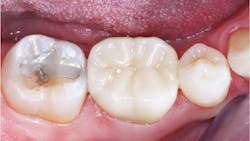

Mesial drift. During life, teeth move toward the mesial. If all the teeth are present without implants, all of them move to the mesial harmoniously, and proximal contacts remain tight. However, a frequently observed malady related to tooth movement when implants are present in the mouth is the mesial contact on an implant-supported posterior crown that opens after a few months of chewing (figure 1).

To reduce or eliminate the challenge caused by the rigidity of implants, the occlusal contacts of the tooth mesial to the implant must be interdigitated, keeping that tooth from moving mesially.